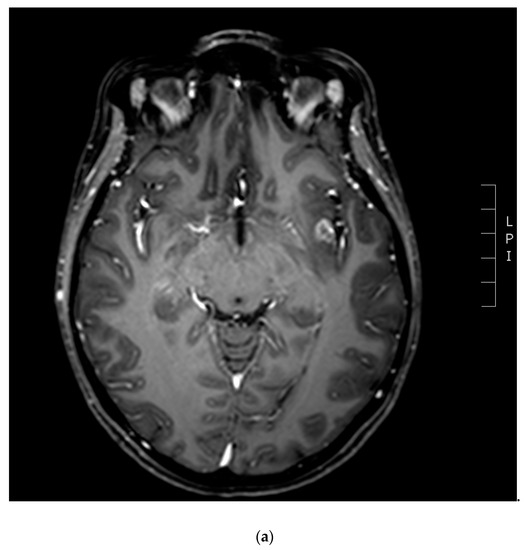

3.1. Diagnostic Imaging Tools in Radionecrosis